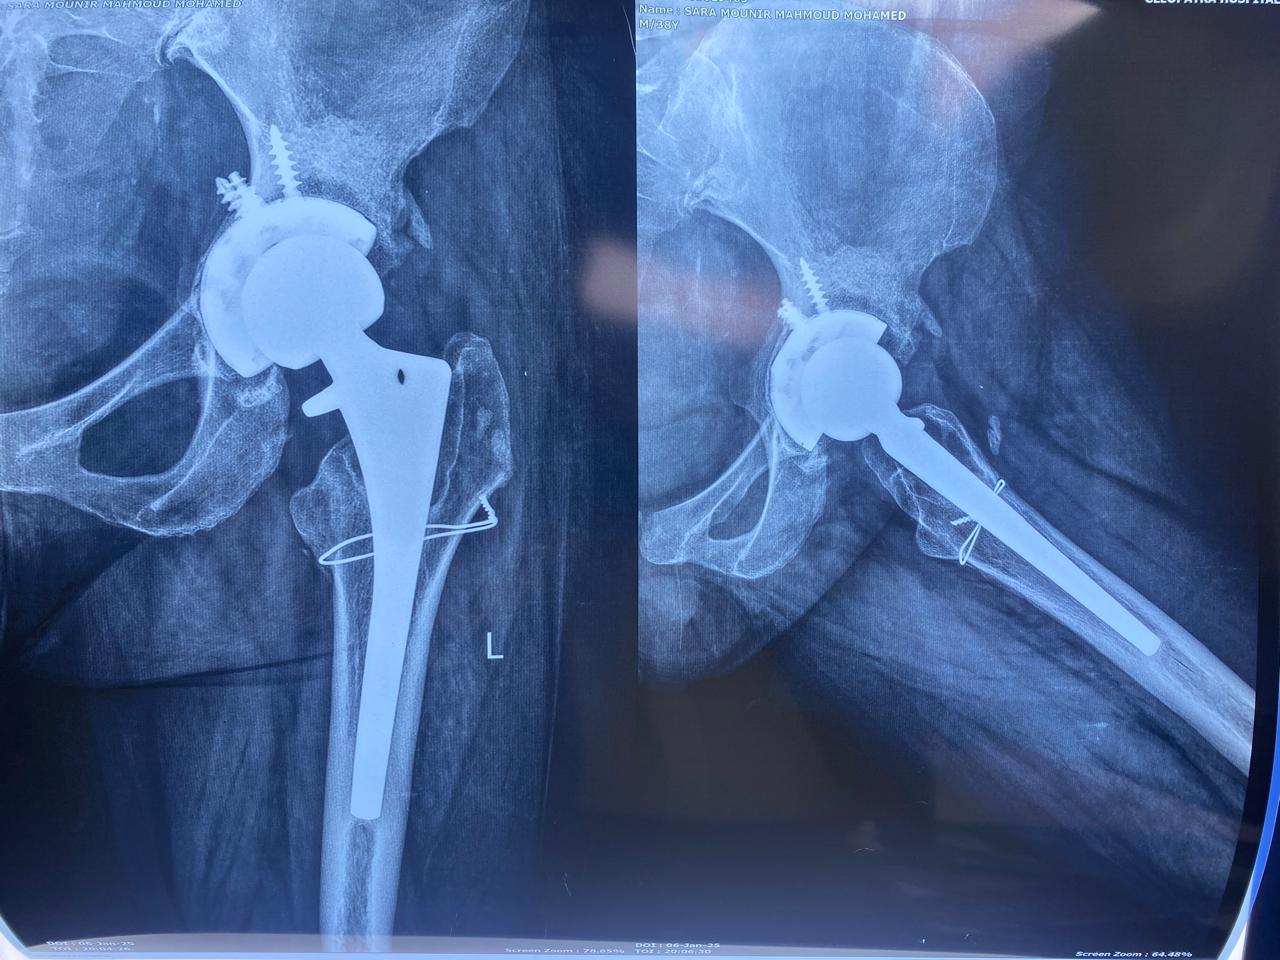

بعد اجراء جراحة تغيير للمفصل مع ترقيع عظمي من بنك العظام

تبين الأشعات ملء الفجوات بالترقيع العظمي.